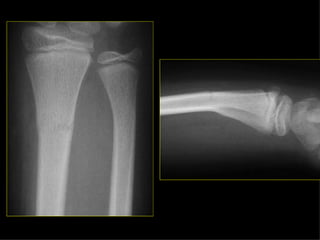

HOMBRO BRAZO CODOANTEBRAZO MUÑECA MANO Monteggia Colles Fx escafoides

HOMBRO BRAZO CODO ANTEBRAZO MUÑECA MANO Monteggia Colles Fx escafoides